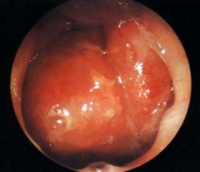

(一)前鼻孔镜检查 :鼻粘膜收敛后经前鼻孔镜可窥到后鼻孔和鼻咽部能发现侵入或邻近鼻孔的癌肿。

(二)间接鼻咽镜检查 :方法简便实用,应依次检查鼻咽的各壁,注意鼻咽顶后壁及两侧咽隐窝要两侧相应部位对照观察,凡两侧不对称的粘膜下隆起或孤立性结节更应引起注意。

(三)纤维鼻咽镜检查 :进行纤维鼻咽镜检查,可先用1%麻黄素溶液收敛鼻腔粘膜、扩张鼻道,再用1%地卡因溶液表面麻醉鼻道,然后将纤维镜从鼻腔插入,一面观察一面向前推进直到鼻咽腔。本法简便,镜子固定好,但后鼻孔和顶前壁观察不满意。